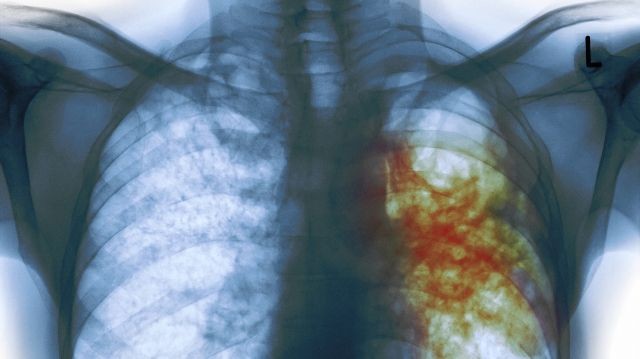

Kifua kikuu ni ugonjwa wa kuambukiza unaosababishwa na bakteria aitwaye Mycobacterium tuberculosis. Ugonjwa huu hasa huathiri mapafu, ingawa unaweza kuathiri sehemu nyingine za mwili kama vile ubongo, uti wa mgongo, na figo. Ni moja ya magonjwa hatari yanayoweza kusababisha vifo ikiwa hayatachunguzwa na kutibiwa kwa wakati.

- Uharibifu wa mapafu au sehemu nyingine za mwili.